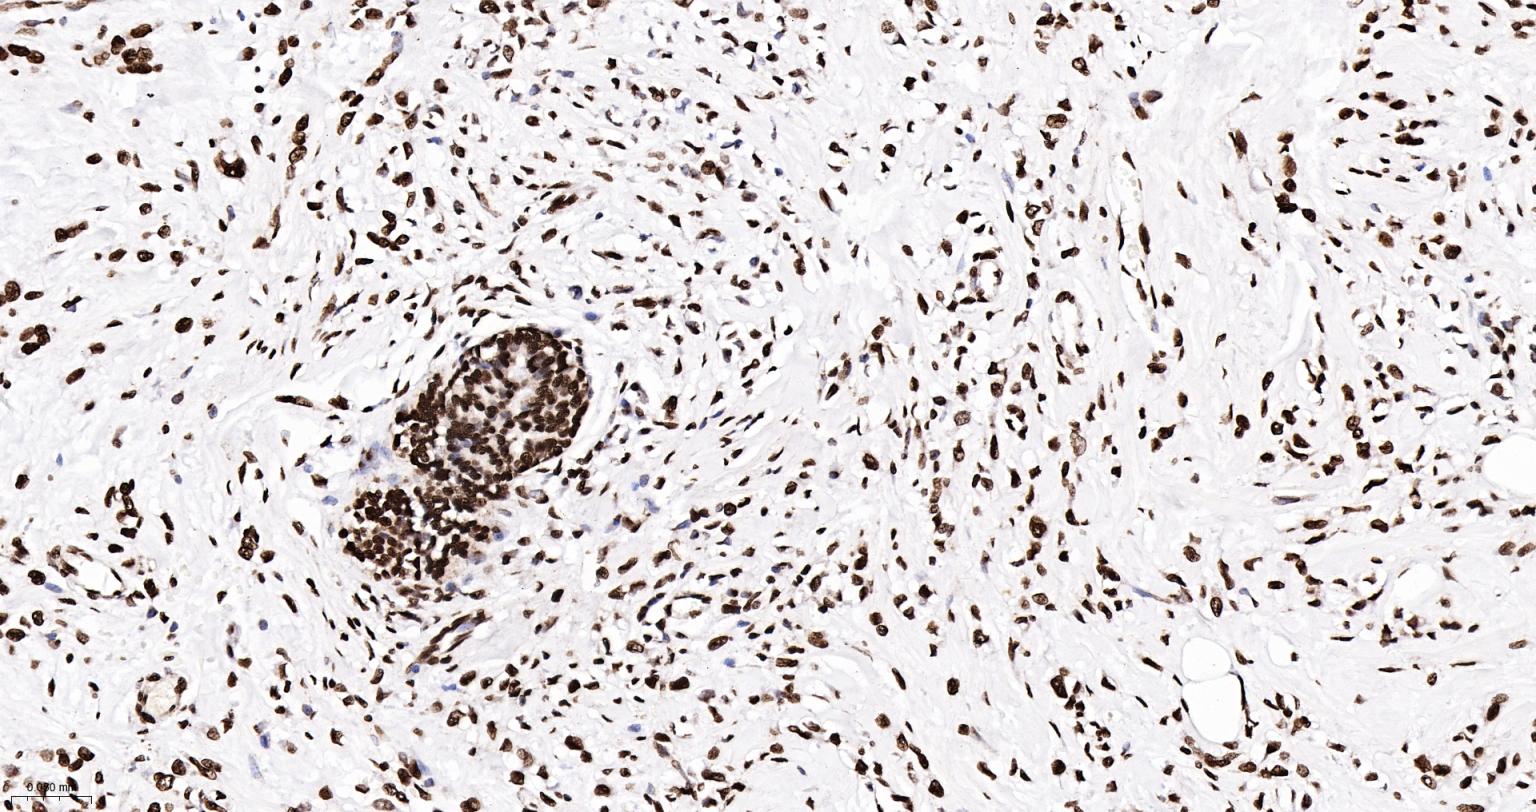

Paraformaldehyde-fixed, paraffin embedded Human Breast Cancer; Antigen retrieval by boiling in sodium citrate buffer (pH6.0) for 15 min; The section was incubated with phospho-SMC1 alpha (Ser957) Monoclonal Antibody, Unconjugated (bsm-62980R) at 1:200 overnight at 4°C, followed by conjugation to the bs-0295G-HRP and DAB (C-0010) staining.